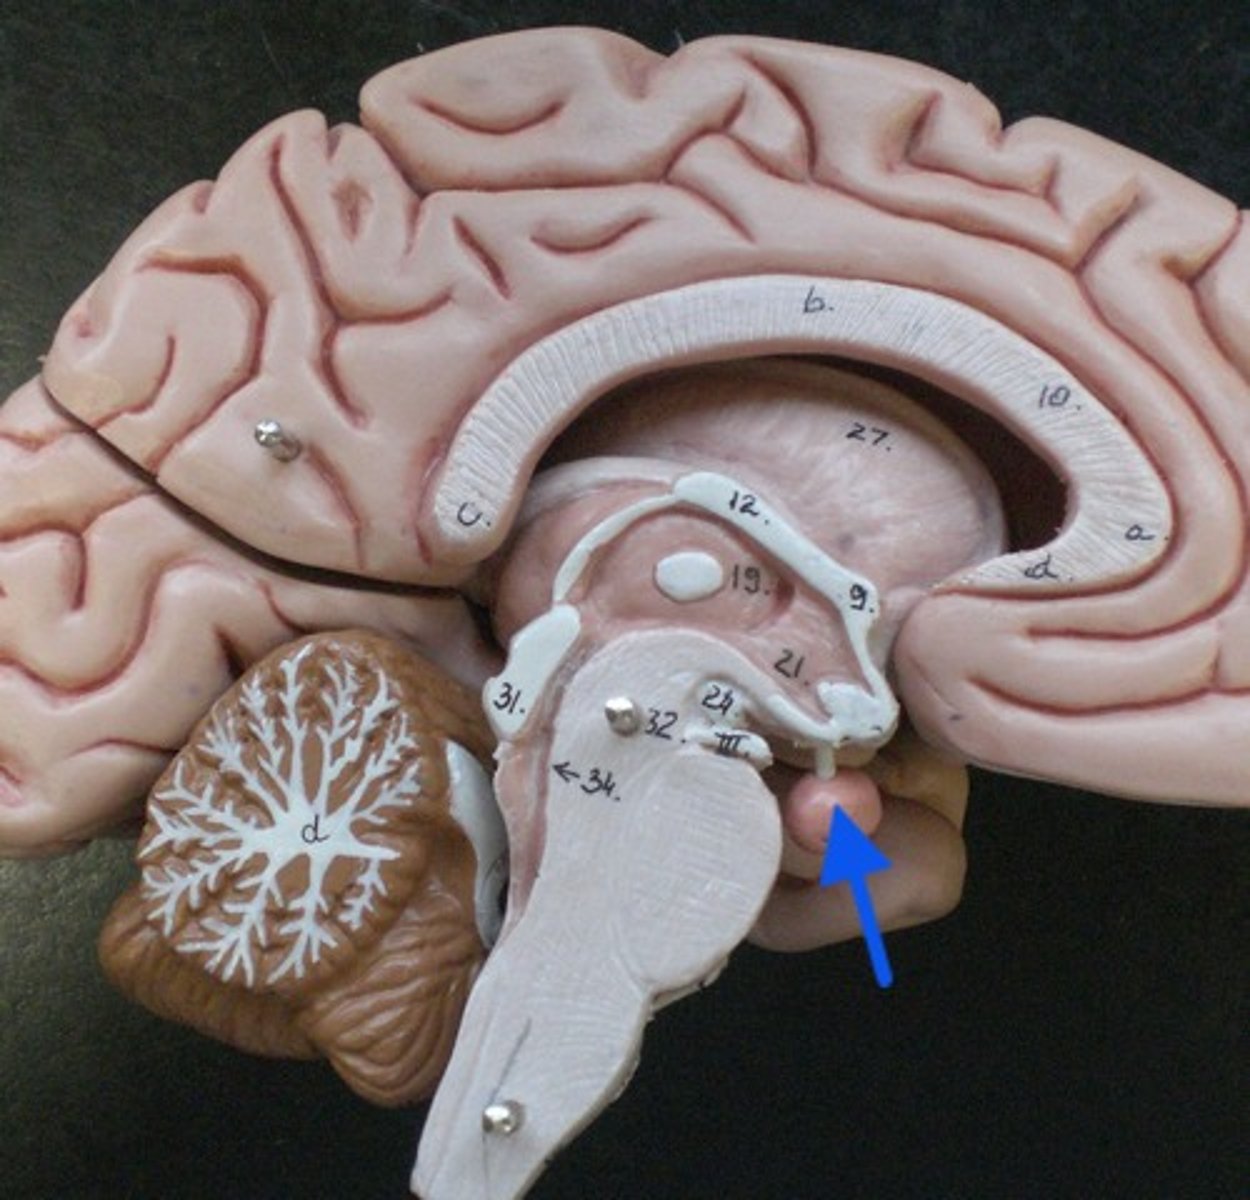

corpus callosum

septum pellucidum

optic chiasm

Interthalamic adhesion

Thalamus

Hypothalamus

Mammillary body

Pituitary gland

Pineal gland

cerebral aqueduct

third ventricle

pons

midbrain

medulla oblongata

oculomotor nerve